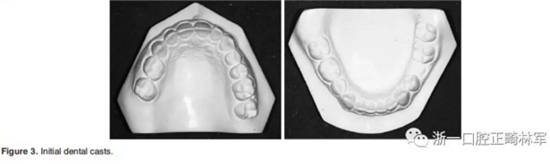

1.基本信息:男性,15歲

2.主訴:左下乳磨牙滯留、微笑不美觀

3.體格檢查:直面型,露齦笑,深覆合、合平面傾斜(Figure 1)。上中線偏右3mm,下中線偏左2mm。磨牙II類關(guān)系,左側(cè)尖牙II類關(guān)系,右側(cè)尖牙I類關(guān)系,左下第二磨牙低位咬合,右上前磨牙缺失。覆蓋率為100%,覆蓋度為4mm。咬合平面重度傾斜,左側(cè)向下移位(Figure 2、3)。